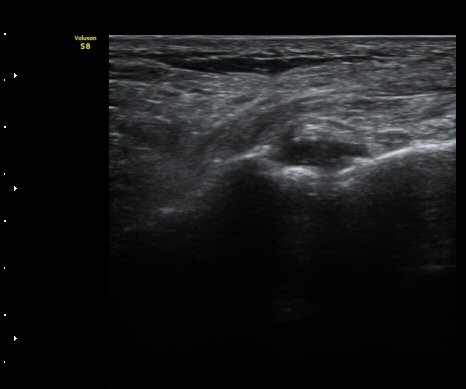

Á¾°ñÀÔ¹æ°ñÀδëÀÇ Á¾´Ü¸é°Ë»ç¿¡¼­ ÀδëÀÇ Á¾°ñ ºÎÂøºÎ ÆÄ¿­ÀÌ °üÂûµÊ(»çÁø 1, 2, 3).